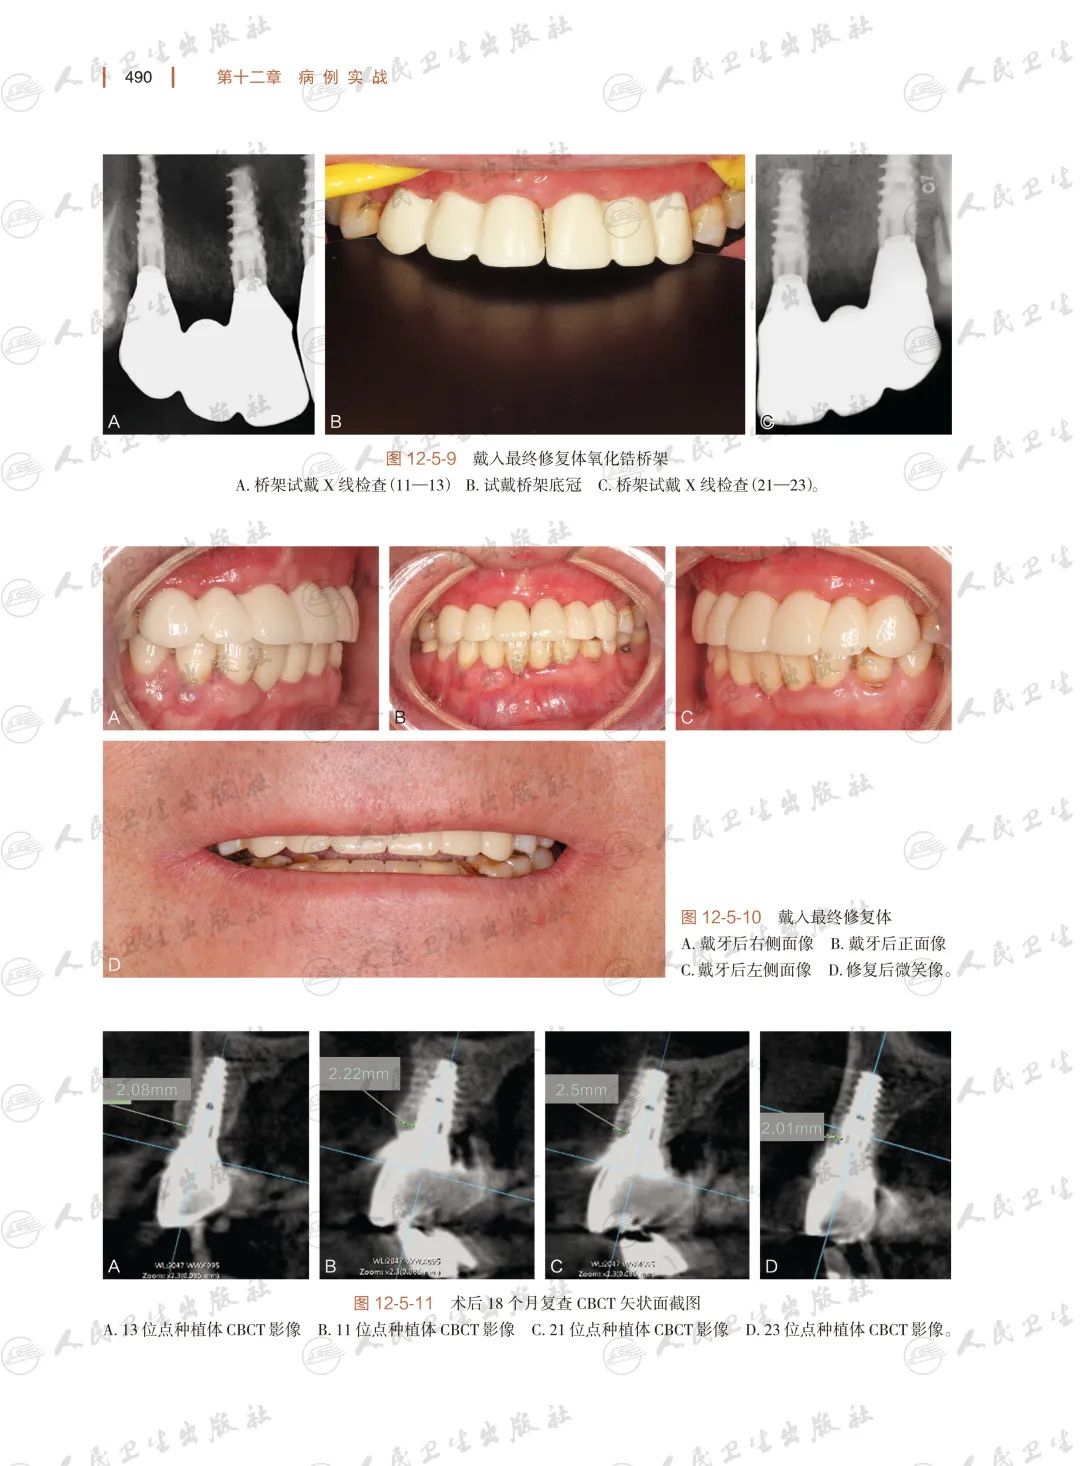

种植体支持的联冠或固定桥的数字化解决方案

病例实战:“以终为始”

——美学区连续多颗牙缺失的数字化口腔种植修复